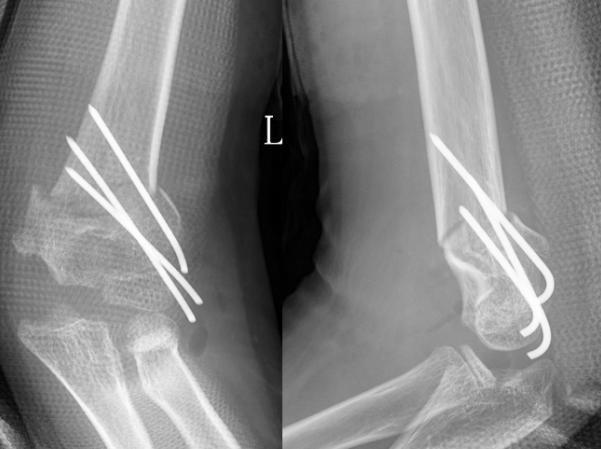

术后X线片示肘内翻矫正满意